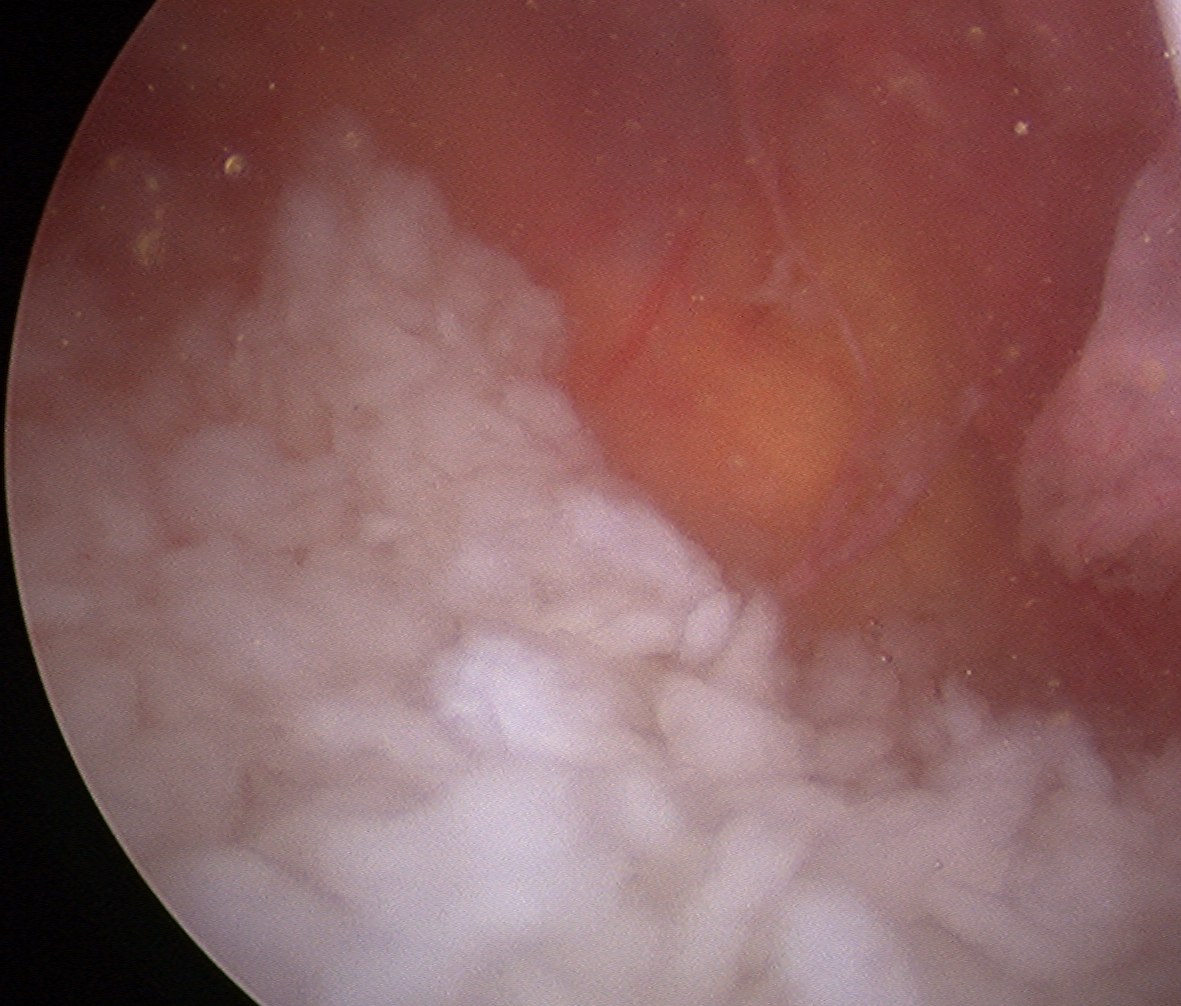

Arthroscopy

Synovial proliferation

- localised or generalised

- can see cartilage growing from synovium

Multiple loose bodies +++